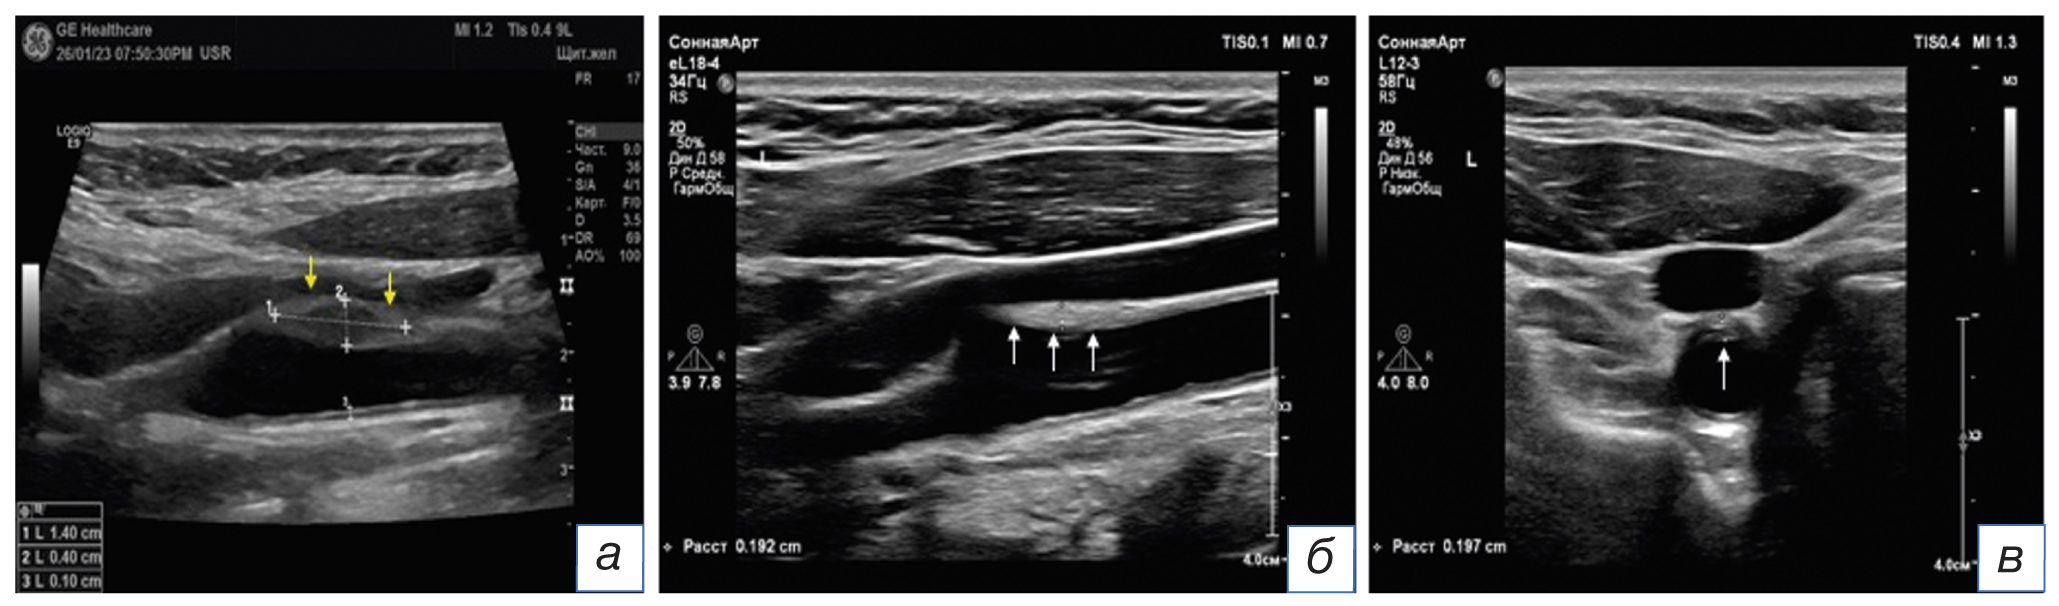

Спустя 2,5 недели от начала симптоматики по результатам УЗИ в бифуркации общей сонной артерии слева выявлены гипо-/средней эхогенности образование с ровной поверхностью, протяжённостью 1,4 см и высотой 4 мм (стеноз просвета около 45% по диаметру), размытость контура адвентиции общей сонной артерии и периваскулярных мягких тканей в области расположения внутрисосудистого образования (рис. 4). Выявленное от 21.01.2023 образование расценено как диссекция, снимки консультированы руководителем лаборатории ультразвуковой диагностики ФГБНУ «Научный центр неврологии»: представленные данные не соответствуют диссекции сонной артерии. Полученные от 15.02.2023 результаты УЗИ с учётом клинико-анамнестических параметров и данных первичного осмотра указывают на воспалительное утолщение (примерно в 2 раза) сосудистой стенки левой общей сонной артерии (TIPIC-синдром) в стадии организации и регресса стенозирующего процесса. Дифференциальная диагностика проводилась между атеросклеротической бляшкой и TIPIC-синдромом.

Рис. 4. Ультразвуковое исследование сонных артерий пациентки с TIPIC-синдромом в динамике: а (продольное сканирование в остром периоде боли в шее от 21.01.2023): по передней стенке в дистальной части и бифуркации общей сонной артерии и устье внутренней сонной артерии визуализируется гипо-/средней эхогенности образование (размеры указаны маркерами 1 и 2) с ровной поверхностью, толщиной 4 мм, приводящее к стенозу по ECST* 40–45%. Обращает внимание размытость контура адвентиции в области выявленного образования (стрелки жёлтого цвета); б (продольное), в (поперечное) сканирование (от 15.02.2023): выявлено гомогенное, средней эхогенности образование (стрелки белого цвета) с ровной поверхностью по передней стенке в дистальной части и бифуркации общей сонной артерии, толщиной 2 мм (стеноз по ECST около 20–25%); контур адвентиции чёткий, признаков отёчности периваскулярных тканей около выявленного образования не отмечено. * Критерий ECST (European Carotid Surgery Trial) — Европейский метод расчёта степени стеноза.

Fig. 4. Ultrasound examination of the carotid arteries of a patient with TIPIC-syndrome in dynamics: а (longitudinal scan in the acute period of neck pain dated 21.01.2023): a hypo-/medium echogenic mass (the sizes are indicated by markers 1 and 2) with a smooth surface, 4 mm thick, resulting in ECST* stenosis of 40–45% is visualised along the anterior wall in the distal part and bifurcation of the common carotid artery and the mouth of the internal carotid artery. The blurring of the adventitia contour in the area of the detected mass (arrows in yellow colour) draws attention; б (longitudinal), в (transverse) scans (dated 15.02.2023): a homogeneous, medium echogenicity mass (white arrows) with a flat surface was detected along the anterior wall in the distal part and bifurcation of the common carotid artery, 2 mm thick (ECST stenosis about 20–25%); the adventitia contour was clear, no signs of perivascular tissue swelling near the detected mass were noted. * ECST criterion — European Carotid Surgery Trial.

Динамика и исходы

Данные магнитно-резонансной и ультразвуковой визуализации подтвердили наличие каротидинии. Проведённое через 20 дней после первого исследования контрольное УЗИ показало положительную динамику в виде уменьшения утолщения внутрисосудистого образования в 2 раза с повышением его эхогенности и улучшения чёткости контура адвентиции (рис. 4), что соответствовало естественной инволюции воспалительного процесса.